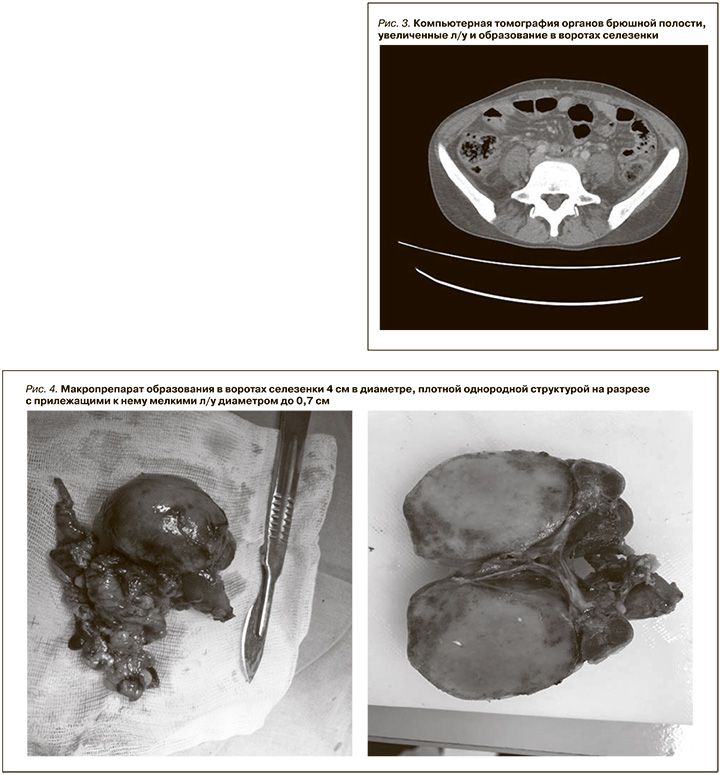

При КТ-исследовании органов брюшной полости (рис. 3) кпереди от ворот селезенки определяется образование овоидной формы с ровными четкими контурами, размером 4,5×4,0×3,0 см, менее активно, чем селезенка, накапливающее контрастное вещество. Рядом – группа умеренно увеличенных л/у с максимальными аксиллярными размерами 23×13 мм. Определяется цепочка умеренно увеличенных парааортальных забрюшинных л/у, наибольший – на уровне ворот левой почки – 20,7×9,7 мм. Правая почка умеренно уменьшена в размерах (9,5×3,0×5,0 см), в паренхиме – мелкие одиночные кисты до 5 мм. Под нижним полюсом левой почки – гематома малого объема (до 5 мл), частично накапливающая контрастное вещество. Селезенка обычной формы и размера (вертикальный размер –8,7 см) с четкими ровными контурами, структура и плотность не изменены. Печень увеличена с ровными контурами, плотность паренхимы – 54,5 HU, паренхима накапливает контрастное вещество равномерно, зоны патологического накопления контрастного вещества не определяются.

Заключение: увеличенные л/у в воротах селезенки, образование в воротах селезенки (увеличенный лимфоузел? добавочная долька селезенки?). Умеренно выраженная ретроперитонеальная лимфаденопатия. Гепатомегалия. Гематома малого объема под нижним полюсом левой почки (после биопсии почки).

С учетом наличия лимфоаденопатии, воспалительного синдрома, данных гистологического исследования почечного биоптата заподозрена БК, в связи с чем через лапароскопический доступ удалено образование в области ворот селезенки, макроскопически выглядящее как добавочная долька селезенки (рис. 4).

В лабораторию доставлено новообразование округлой формы диаметром 4 см, темно-коричневого цвета, на разрезе к нему прилежали мелкие л/у диаметром до 0,7 см. Гистологически оба препарата имели строение л/у с измененными фолликулами, гиалинозом и отложением оптически плотных масс (амилоид?). Паренхима была представлена гиперплазированной лимфоидной тканью с примесью плазматических клеток. Была заподозрена БК, смешанный вариант.